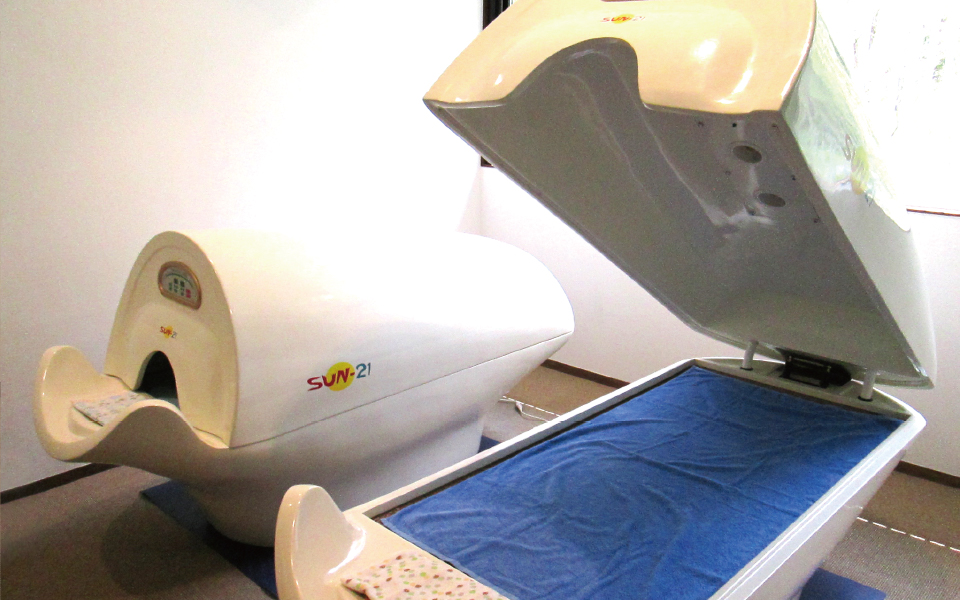

どんな機械?

マイクロ波発生装置(SHT)は2.45GHz、出力300-700Wで43℃まで体温を上げてガン細胞の周辺の血管を破壊して縮小させ、健常な細胞を活性化します。

状態によって回数、間隔は変動しますが、マイクロ波を使う場合は、1回10秒を30分、1クール(20回)を目安に続けて、医師の診察を受けて状態を確認してください。

寛解・完治前に辞めてしまうと、がん細胞にマイクロ波への抵抗がつくため効果が薄くなります。

誰がやるの?

マイクロ波発生装置は、お客様自身に操作して頂きますが、初回は専門の講習を受けたスタッフが丁寧に教えます。

身体的理由等で操作が出来ない、難しい場合は専門スタッフが代わりに操作します。